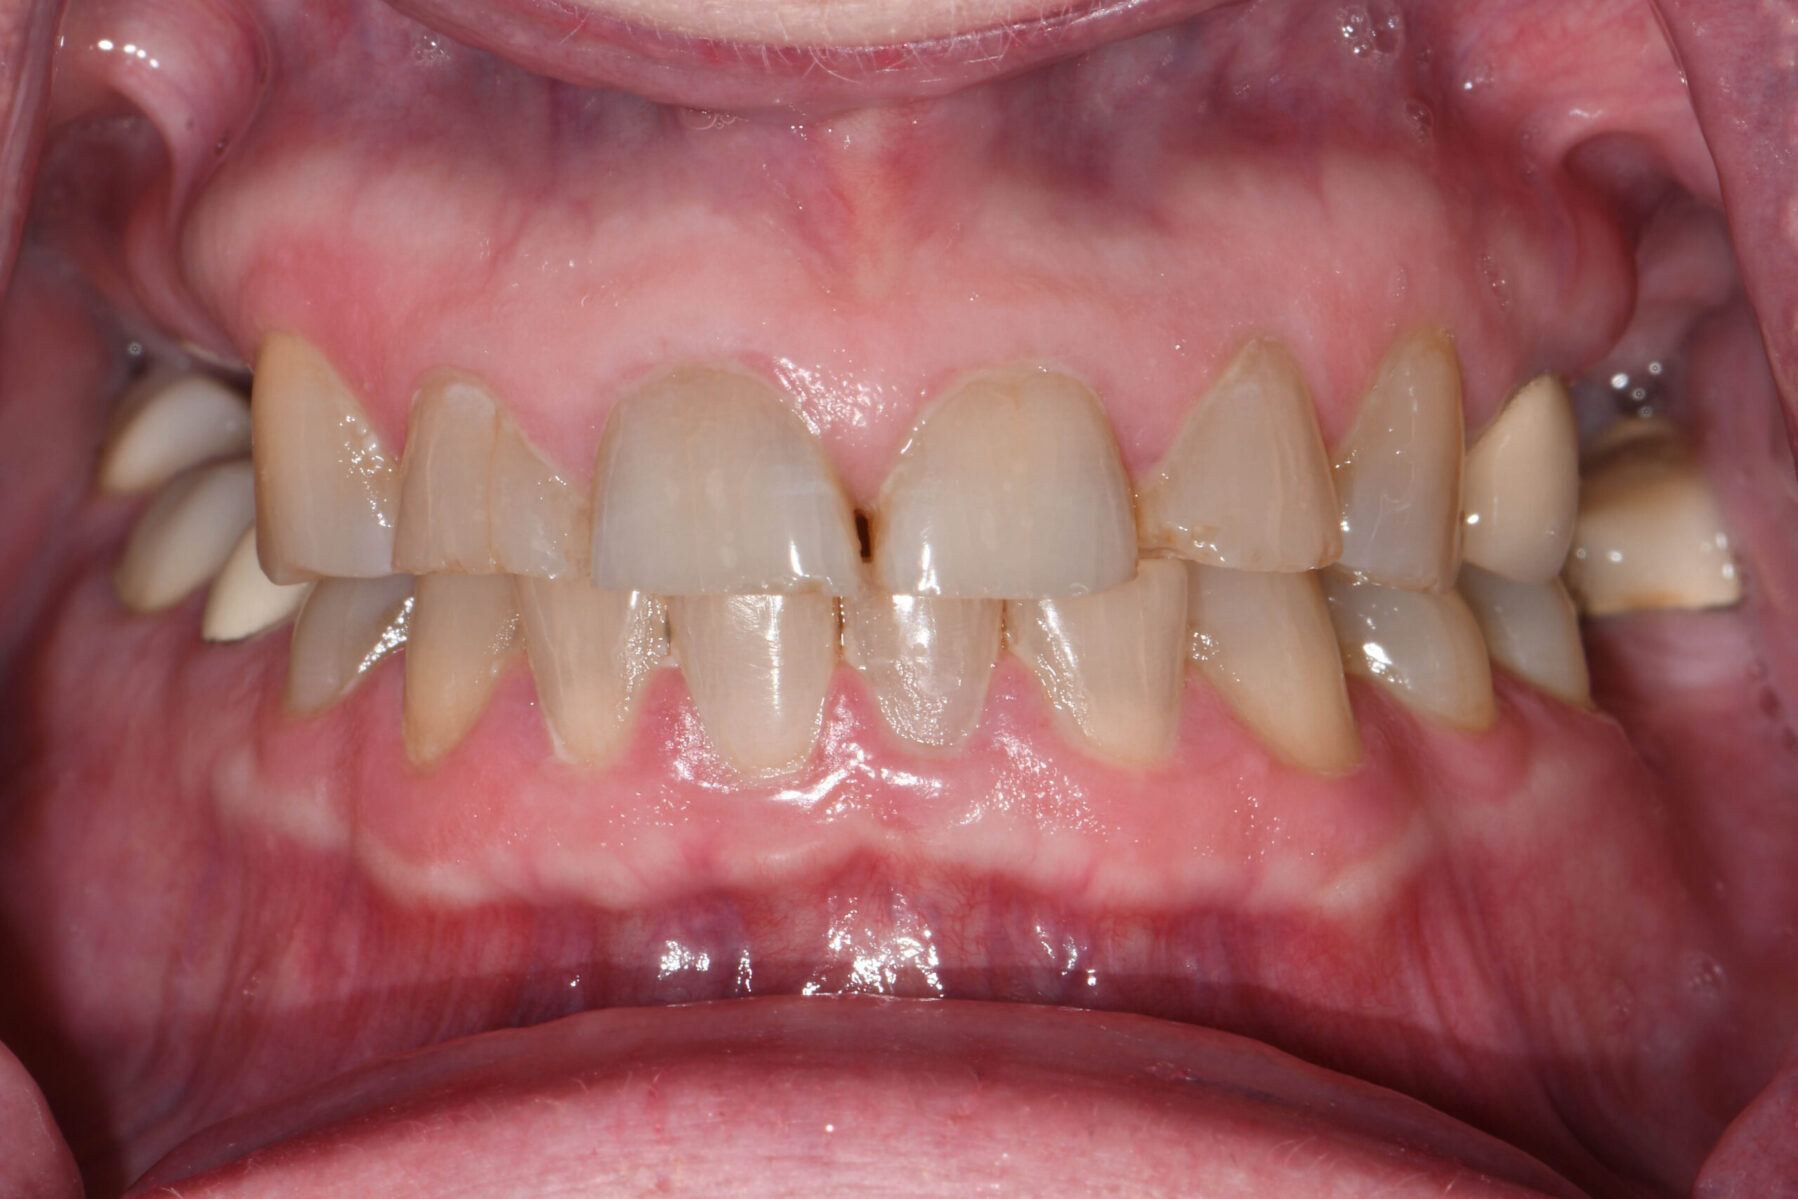

Full mouth rehabilitation encompasses a range of restorative dental procedures aimed at restoring the function, health, and esthetics of your entire mouth.

This may involve the use of crowns to protect and reinforce weakened teeth, dental implants to replace missing teeth, and veneers to improve the appearance of discolored or damaged teeth. Each treatment is tailored to match the color, shape, and size of your natural teeth, ensuring a cohesive and beautiful smile.

• Restoring multiple missing or damaged teeth for improved function and stability

• Restoring worn down teeth from grinding, clenching, or traumatic occlusion